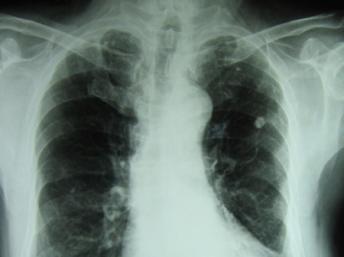

Lây nhiễm đến gần 10 triệu người và khiến gần 1,5 triệu người chết trên thế giới hàng năm, bệnh lao vẫn là một trong các căn bệnh đáng sợ đối với nhân loại. (DR)

Việc xuất hiện các loại vi trùng lao kháng thuốc và tình trạng điều trị yếu kém tại nhiều khu vực và quốc gia khiến lao tiếp tục là một trong những bệnh truyền nhiễm gây tử vong hàng đầu trên thế giới, với gần 1,5 triệu người/năm. Riêng ở Việt Nam, theo một số liệu thống kê trong nước, mỗi năm có khoảng gần 200.000 người mắc lao, trong đó có khoảng 5.000 đến 6.000 người bị vi trùng lao kháng thuốc, và gần 30.000 người chết do bệnh lao nói chung.

Bác sĩ Đinh Xuân Anh Tuấn lưu ý bệnh lao là một trong các bệnh thông thường nhất. Theo một số thống kê gần đây của Liên Hiệp Quốc, 1/3 nhân loại đang hoặc đã bị nhiễm vi trùng lao. Lao là loại vi trùng rất dễ lây lan. Dù bệnh lao không còn gây tử vong ở mức độ rất cao như xưa nữa, nhưng vẫn còn là nguyên nhân tử vong lớn.